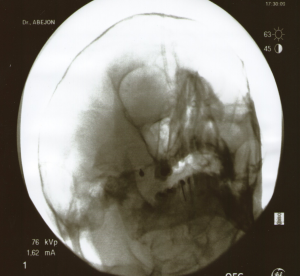

El paciente se coloca en decúbito supino, con la cabeza ligeramente en hiperextensión. Con el arco de fluoroscopia en posición anteroposterior AP se rota en dirección caudal hasta obtener una visión submentoniana, realizando entonces proyección oblicua ipsilateral (10-15º) hacia el lado a tratar hasta que se encuentre el foramen oval. Una referencia útil, si resulta complicada la visualización del mismo, es trazar una línea imaginaria que una la apófisis estiloides de la mandíbula con la última pieza dentaria del maxilar superior. Si las ramas a tratar son la segunda y la tercera dirigiremos la aguja en visión túnel hacia la parte central del foramen oral. (entrando a nivel de la piel a dos dedos de la comisura bucal) y si es la primera rama, dirigiremos la aguja en visión túnel a la parte interna de dicho foramen (a tres dedos de la comisura bucal), por la localización de las ramas como se ha descrito en anatomía. Una vez localizado el foramen oval y señalizado el punto de entrada en la piel, se fija la cabeza del paciente para evitar la movilización de la misma durante el procedimiento y se procede a realizar una sedación profunda.. Una vez introducida la aguja y antes de profundizar, es conveniente introducir un dedo en la boca del paciente para asegurarnos que no se ha perforado la mucosa oral, lo que conlleva el riesgo de contaminación y la posibilidad de producir una meningitis. La aguja se avanza hasta la entrada en el agujero oval, que se suele apreciar un aumento de la resistencia, en ese momento se realiza una proyección lateral para comprobar la profundidad y la correcta colocación en la cavidad de Meckel, no debiendo superar la punta el plano del clivus. Una vez comprobada la adecuada situación se procede a la estimulación, primero se realiza una estimulación motora a 0.6v comprobando que no existe contracción del masetero si se obtiene estímulo motor, la aguja se avanza cuidadosamente 1 ó 2mm. Se procede a despertar al paciente y con un estímulo sensitivo se comprueba la parestesia en la rama adecuada. Nuevamente se profundiza la sedación y se realiza la lesión. Estimulación sensitiva: (50Hz) desde notar parestesias entre 0.1- 0.5v. Estimulación motora: (2Hz) no debe haber contracción del musculo masetero con 0.7-1v (excepto si se está estimulando la tercera rama). Se realiza varias lesiones con radiofrecuencia convencional (1ª lesión 60s a 60º, 2ª lesión 60s a 65º y 3ª lesión 60s a 70º).